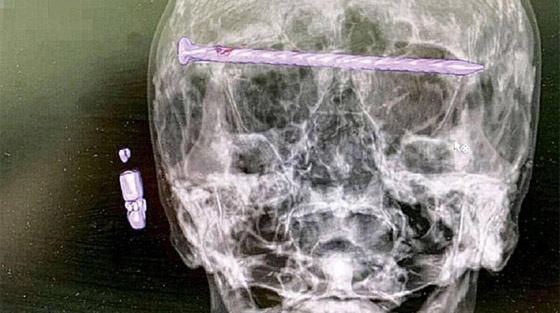

اكتشف أطباء روس مفاجأة صادمة عند فحص رجل، يبلغ من العمر 78 عاما، إذ تبين وجود مسمار طوله 15 سم مستقرا في رأسه.

وعند التصوير المقطعي، تبين وجود مسمار طوله 15 سم يمر بالصدغ الأيمن عبر محجر العين إلى الصدغ الأيسر، بينما قال الأطباء إن الوضع ازداد سوءا بسبب تلف الجافية في الدماغ والضغط على مقلة العين.